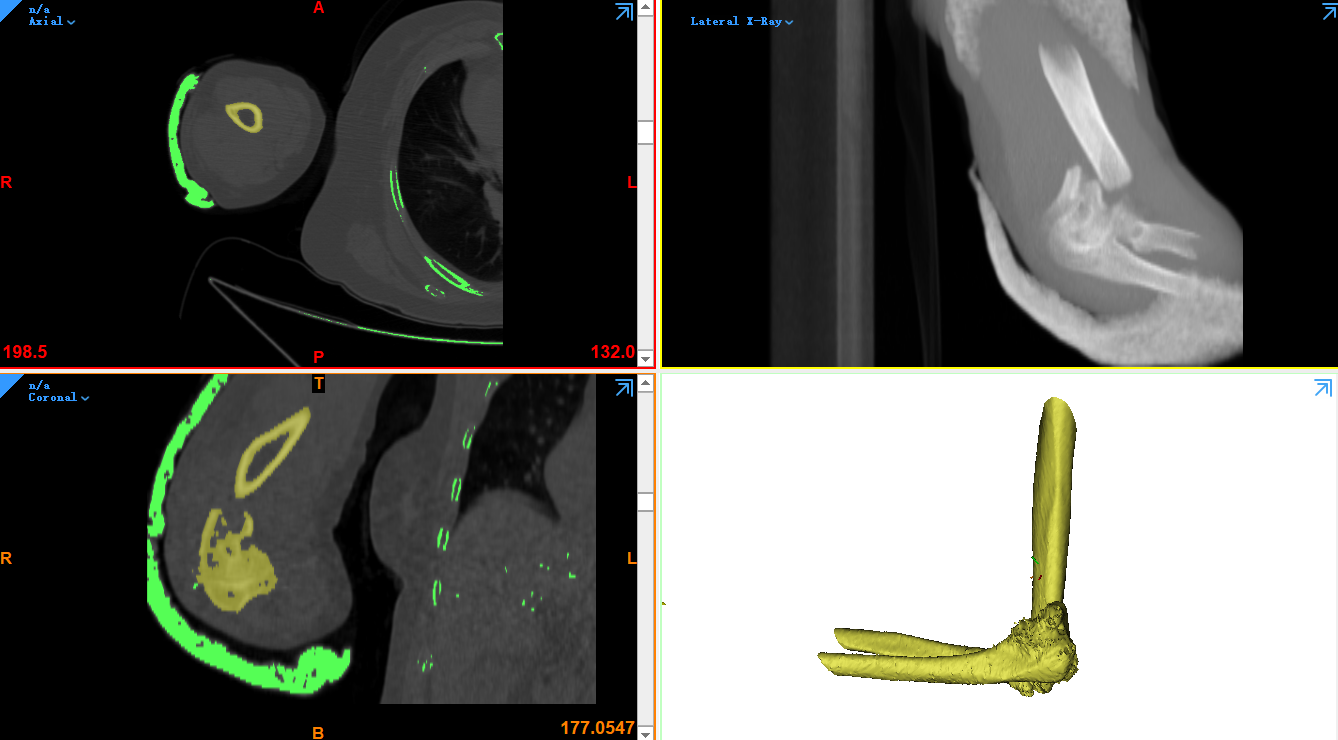

另外,醫(yī)療領(lǐng)域3D技術(shù)同樣起到不可代替的作用。例如根據(jù)CT斷面圖像,構(gòu)建人體骨骼模型的方案,就離不開3D技術(shù)的支持。根據(jù)CT獲取的三維模型不僅可以直觀的觀察病人的病情,還能夠制作手術(shù)導(dǎo)板,將再次降低醫(yī)療手術(shù)的風(fēng)險。除此之外先前一段時間被炒得火熱的胎兒打印話題,則是根據(jù)三維彩超數(shù)據(jù)斷面數(shù)據(jù)創(chuàng)建的胎兒模型,而后或進(jìn)行3D打印或進(jìn)行水晶內(nèi)雕生成胎兒模型的3D技術(shù)。

(正在根據(jù)CT數(shù)據(jù)創(chuàng)建三維模型)